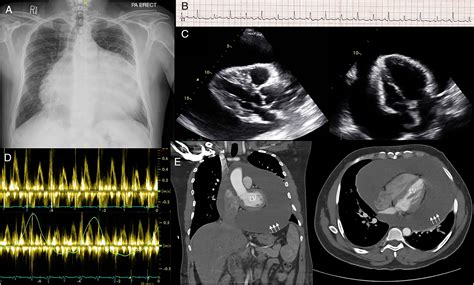

Diagnosing pericardial effusion involves a combination of clinical evaluation, imaging studies, and laboratory tests. Common diagnostic tools include:

• Echocardiography: This is the gold standard for diagnosing pericardial effusion. It provides real-time images of the heart and pericardium, allowing for the detection and measurement of fluid accumulation.

• Chest X-ray: While not as sensitive as echocardiography, a chest X-ray can sometimes reveal an enlarged cardiac silhouette, suggesting pericardial effusion.

• CT Scan or MRI: These imaging modalities can provide detailed views of the pericardium and surrounding structures, aiding in the diagnosis and assessment of pericardial effusion.

Diagnosing cardiac tamponade involves a rapid assessment of the patient's hemodynamic status and the use of imaging studies. Key diagnostic tools include:

• Echocardiography: This is the primary diagnostic tool for cardiac tamponade. It can visualize the pericardial effusion and assess its hemodynamic impact on the heart.

• Chest X-ray: While not as sensitive as echocardiography, a chest X-ray can sometimes reveal an enlarged cardiac silhouette.

• CT Scan or MRI: These imaging modalities can provide detailed views of the pericardium and surrounding structures, aiding in the diagnosis and assessment of cardiac tamponade.

• Electrocardiogram (ECG): An ECG can show low voltage and electrical alternans, which are characteristic of pericardial effusion and tamponade.